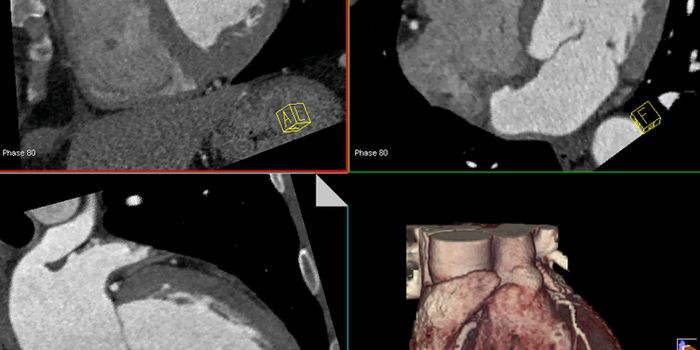

MAR 21, 2016CardiologyNoninvasive CT scans are far better at finding clogged arteries that can trigger a heart attack than the exercise stress ...

FEB 26, 2016CardiologyHeart disease is the leading cause of death nationally and globally. Using the most advanced 3D printing technology, sci ...